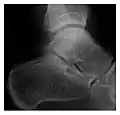

Figure 6: Subtle anterior talar fracture in a 39-year-old man presenting with ankle pain after a fall. (a) Anteroposterior radiograph shows a subtle oblique radiolucent line through the talus (white arrows). (b) Sagittal CT reformation confirms the presence of an anterior talar fracture with cortical offset (black arrow). Avulsion fractures, which consist of a detached bone fragment resulting from a ligament or tendon pulling away from the bone, may also present with subtle radiographic signs. Tiny osseous fragments near the presumed attachment site of a ligament suggest this diagnosis. Common sites are the lateral tibial plateau (the Segond fracture), the spinal tuberosity of the tibia resulting from anterior cruciate ligament avulsion, and the ischial tuberosity.[1]